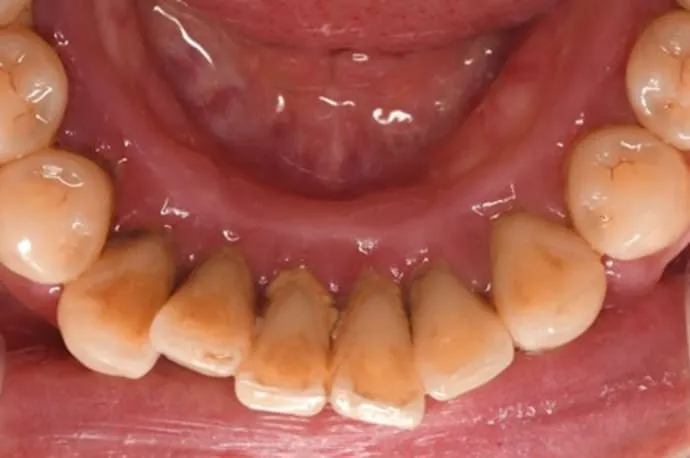

歯周基本治療の症例

治療前

治療後

歯周基本治療後の状態です。治療により歯ぐきの腫れや出血が改善し、炎症が落ち着いている様子が確認できます。歯石の除去によって、口臭やお口の中の不快感も軽減しています。

※歯周病によって歯ぐきが腫れていた場合、炎症が治まることで歯ぐきが引き締まり、治療前より下がったように見えることがあります。

※歯石除去後、一時的に知覚過敏の症状が出る場合があります。